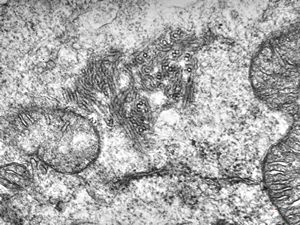

M,33y. | blood - hairy cell leukemia- ribosome-lamella complexin tricholeukocyte

M,41y. | hairy cell leukemia - spleen - ribosome-lamella complex in tricholeukocyte